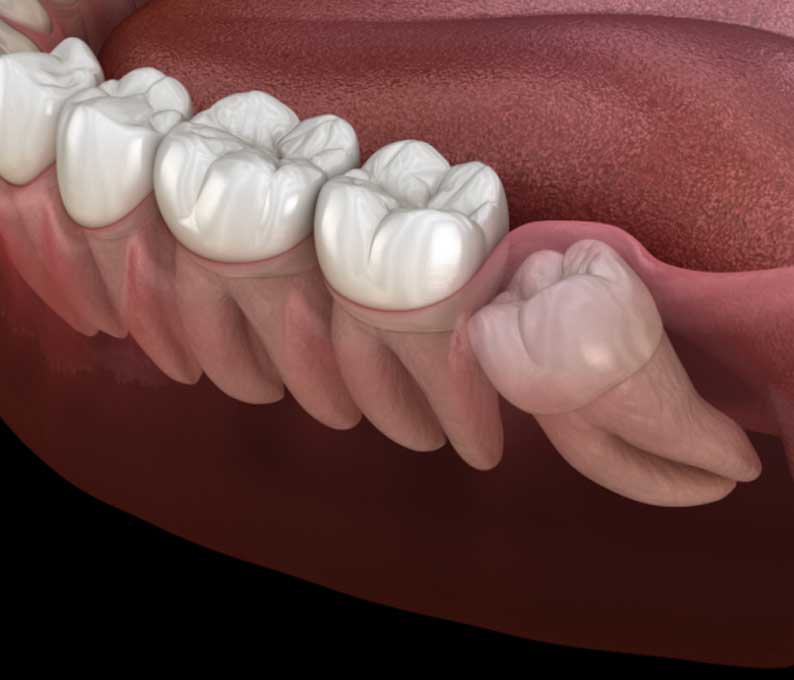

Wisdom teeth often cause pain, swelling, or misalignment when they do not have enough space to emerge properly. Our wisdom tooth extraction procedure removes these third molars safely, preventing future dental problems.

When a tooth remains trapped beneath the gum line, it is considered impacted. Impacted tooth extraction is a surgical procedure to remove the affected tooth and prevent complications such as infection, pain, and damage to surrounding teeth.

An operculectomy is the removal of excess gum tissue (operculum) that partially covers a tooth, particularly a wisdom tooth. This procedure reduces the risk of infection and discomfort caused by trapped food and bacteria.

In cases where a tooth is stuck beneath the gums, surgical exposure helps guide the tooth into its proper position. This is commonly performed as part of orthodontic treatment to align impacted teeth properly.